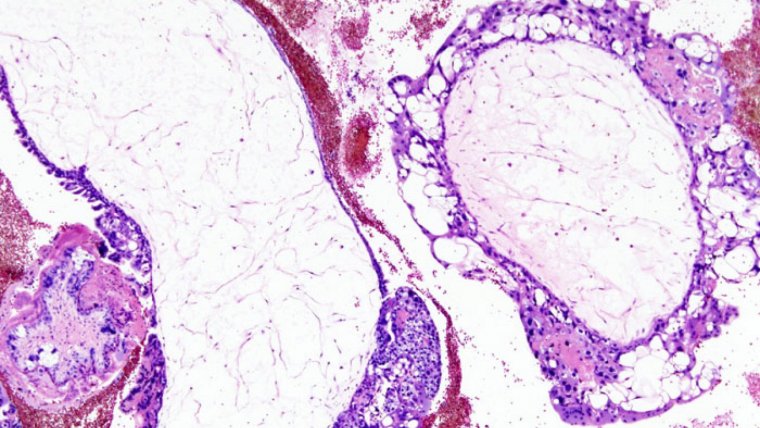

La mola hidatiforme, que como hemos dicho previamente también es llamada “embarazo molar”, es una alteración del embarazo caracterizada por el crecimiento anormal de los trofoblastos, que son las células a partir de las cuales se desarrolla la placenta en condiciones normales.

El embarazo molar forma parte de un grupo de alteraciones conocidas como “enfermedades trofoblásticas gestacionales”. Se trata de un tipo de tumor que por lo general es benigno, si bien la proliferación de células anormales puede dar lugar a cáncer. Describiremos de forma detallada las posibles complicaciones de la mola hidatiforme más adelante.

Existen dos tipos de mola hidatiforme: la completa y la parcial. Hablamos de embarazo molar completo cuando el tejido fetal no llega a desarrollarse en ningún grado y la placenta se encuentra inflamada, tiene un aspecto poco habitual y forma quistes llenos de líquido. En los casos de mola completa en ocasiones ni siquiera se forma la placenta.

Por contra, en la mola hidatiforme parcial es posible observar tejidos placentarios normales, si bien combinados con otros de naturaleza patológica. De hecho puede que incluso se forme parcialmente el feto, si bien éste no podrá sobrevivir a la gestación y lo más probable es que sea expulsado por el organismo de la madre por medio de un aborto espontáneo durante el primer trimestre del embarazo.

A pesar de que la mayoría de molas hidatiformes son tumores benignos, en ocasiones pueden complicarse y dar lugar al coriocarcinoma, un tipo de cáncer de las células trofoblásticas de la placenta (Cotran et al., 2005). En cualquier caso es relativamente poco habitual que el embarazo molar progrese hasta convertirse en un tumor maligno, ya que esta complicación se da en el 10% de casos más o menos.